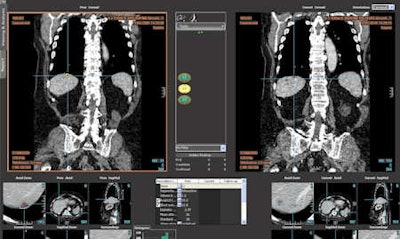

Follow-up of a hepatic lesion with the LMS platform (abdominal radiology) now in routine practice at La Fe Hospital.

Follow-up of a hepatic lesion with the LMS platform (abdominal radiology) now in routine practice at La Fe Hospital.In a further step, the hospital aims to use the software in the evaluation of tumor necrosis to follow tumor response to therapy. To do this, methods to properly measure enhancement, thus automatically measure viable tumor, will need to be explored and established.